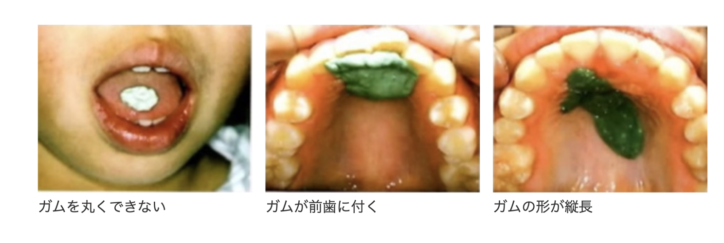

舌の機能が足りない例

低位舌で舌の力が正常でない場合、下記の様になってしまいます。「ガムトレーニング」は正しい方法で訓練しなければ舌の機能が回復しません。